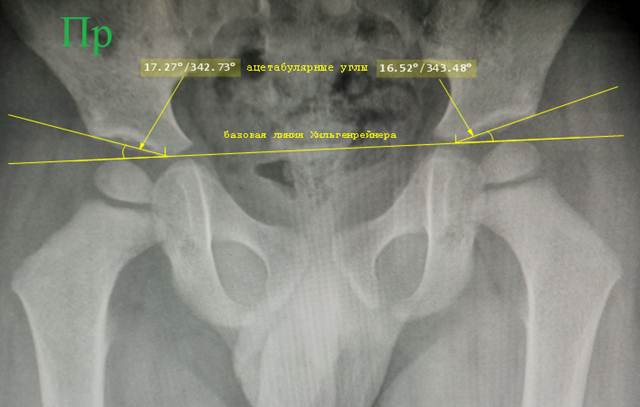

Ацетабулярный

угол. В месте контакта линии

Хильгенрейнера с тенью подвздошной кости ставится точка. Если зона контакта

линии с тенью кости представляет собой отрезок, что имеется у старших детей, то

точку надо ставить в его середине, прямо на тени кости. От этой точки проводят

линию к верхнему краю вертлужной впадины – линию крыши врадины. Здесь нужно быть внимательным: если у ребенка

начал визуализироваться её окостеневающий край (лимбус), то линию надо

проводить касательно к нему, а не к основному массиву кости. Угол между

проведенной линией и линией Хильгенрейнера и будет ацетабулярным углом.

Снимок таза ребенка 4 лет. Проведена линия Хильгенрейнера по нижним краям тел

подвздошных костей. Линия ацетабулярного угла начинается в точке контакта линии

Хильгенрейнера с тенью подвздошной кости.

Снимок

таза ребенка 14 лет. Линия

Хильгенрейнера привязывается к выступам с горизонтальными просветами, заметным

на внутреннем контуре тазового кольца.

Просветы выступов соответсвуют

нижним краям тел подвздошных костей. Точка начала линии ацетабулярного угла

находится на линии Хильгенрейнера посередине тени тела подвздошной кости.